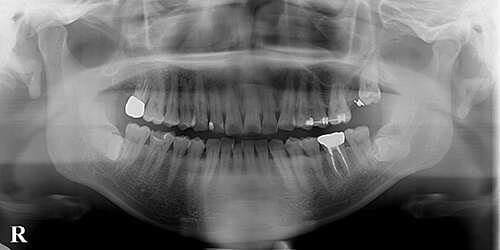

【治療中】

部分矯正での左上8(親知らず)挺出中です。時間経過しても挺出が起こらず、逆に456(第1種臼歯、第2小臼歯、第1大臼歯)が後ろに倒れてしまうこと(8(親知らず)が骨性に癒着している可能性)もあるので注意が必要です。また挺出が始まったとしても456(第1種臼歯、第2小臼歯、第1大臼歯)が後ろに倒れてしまうこと(アンカー不足の可能性)もあるのでこれも注意が必要です。